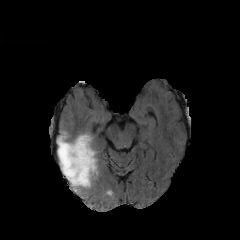

We observe that the generated normal-looking from ANT-GAN can also be used to directly segment the image, since the only difference between a synthesized normal-looking image and its real abnormal counterpart is region with the lesion. To illustrate this, we calculate the absolute difference between x𝑥x and 𝒢A2N(x)subscript𝒢A2N𝑥\mathcal{G}_{\rm{A2N}}(x) and show the segmentation after binary thresholding at 0.1 in Figure 9.

Refer to caption

(a) Tumor x𝑥x

(b) 𝒢A2N(x)subscript𝒢A2N𝑥\mathcal{G}_{\rm{A2N}}(x)

(c) Prediction

(d) Label

Figure 9: Example segmentation obtained by taking the absolute difference between the real tumor MRI x𝑥x and the generated normal-looking MRI 𝒢A2N(x)subscript𝒢A2N𝑥\mathcal{G}_{\rm{A2N}}(x), after binarization at a preset threshold.